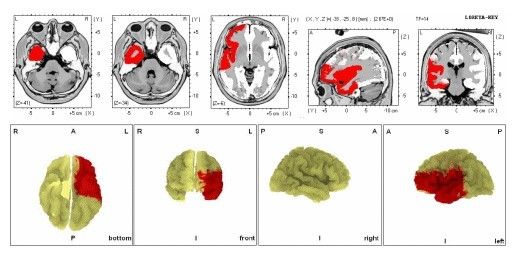

According to the images of the manufacturing and clinical testing stages, up to this stage, we had no impairment of vital signs, including breathing and heart rate, and with the feature of our refractive injections, we also prevented an increase in blood pressure, and this stage of the formulation was truly an amazing idea.